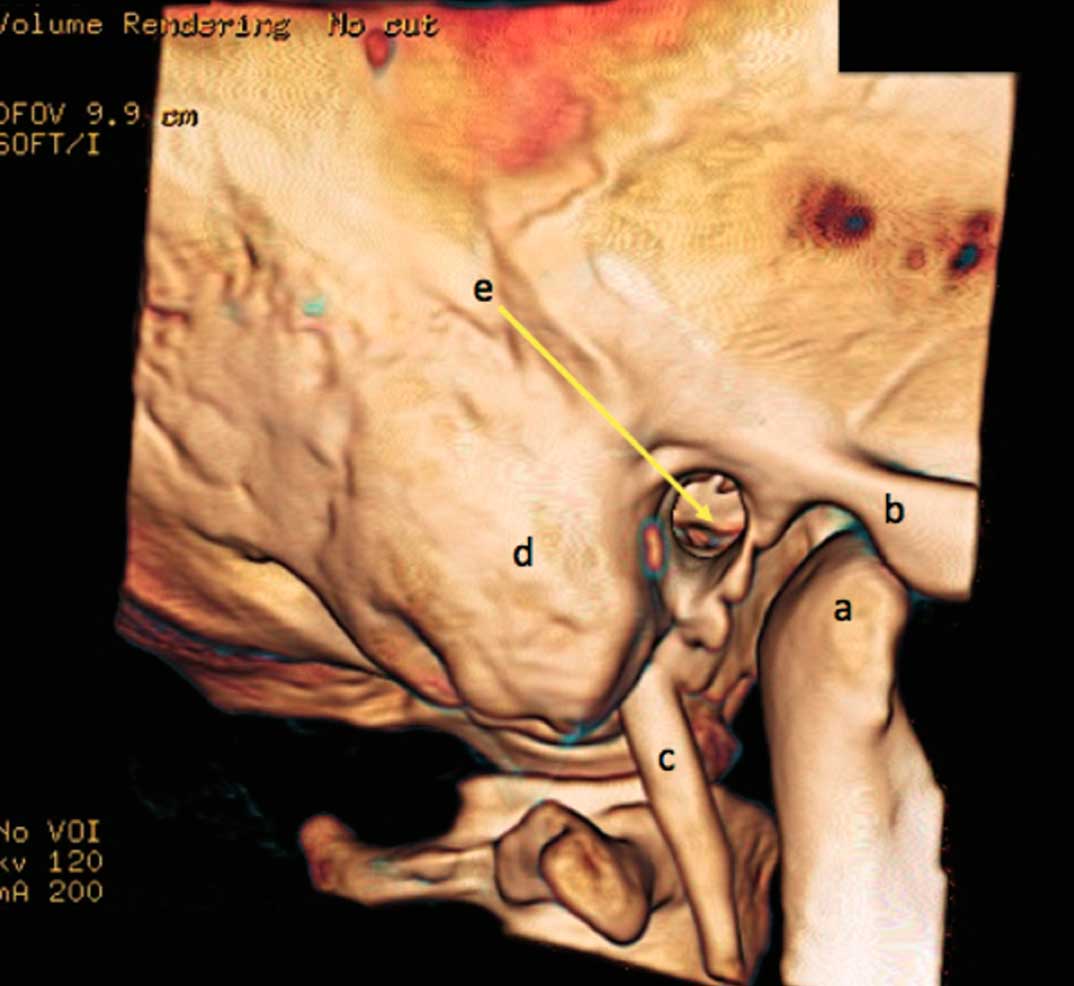

A anatomia do osso temporal é complexa e demanda um conhecimento anatômico profundo. A junção entre cirurgia e imagem ajuda no processo de aprendizado da anatomia tridimensional e das técnicas cirúrgicas. Imagens do osso temporal em alta definição possuem papel importante no treinamento de dissecção. Estes cursos são o primeiro passo para aquisição do conhecimento em cirurgia da base do crânio para operar neurinomas, meningeomas e tumores do glomus jugular.